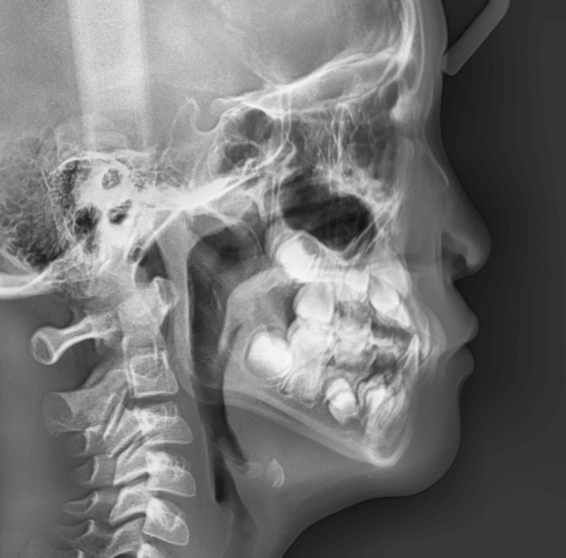

| 年齢・性別 | 11歳1ヶ月の女性 |

|---|---|

| 主訴 | 口元の突出感と歯並びが気になり、将来的な咬合状態を整える目的で来院された患者様です。 |

| 治療期間・回数 | 2年6ヶ月・25回 |

| 費用 | 720,000円 |